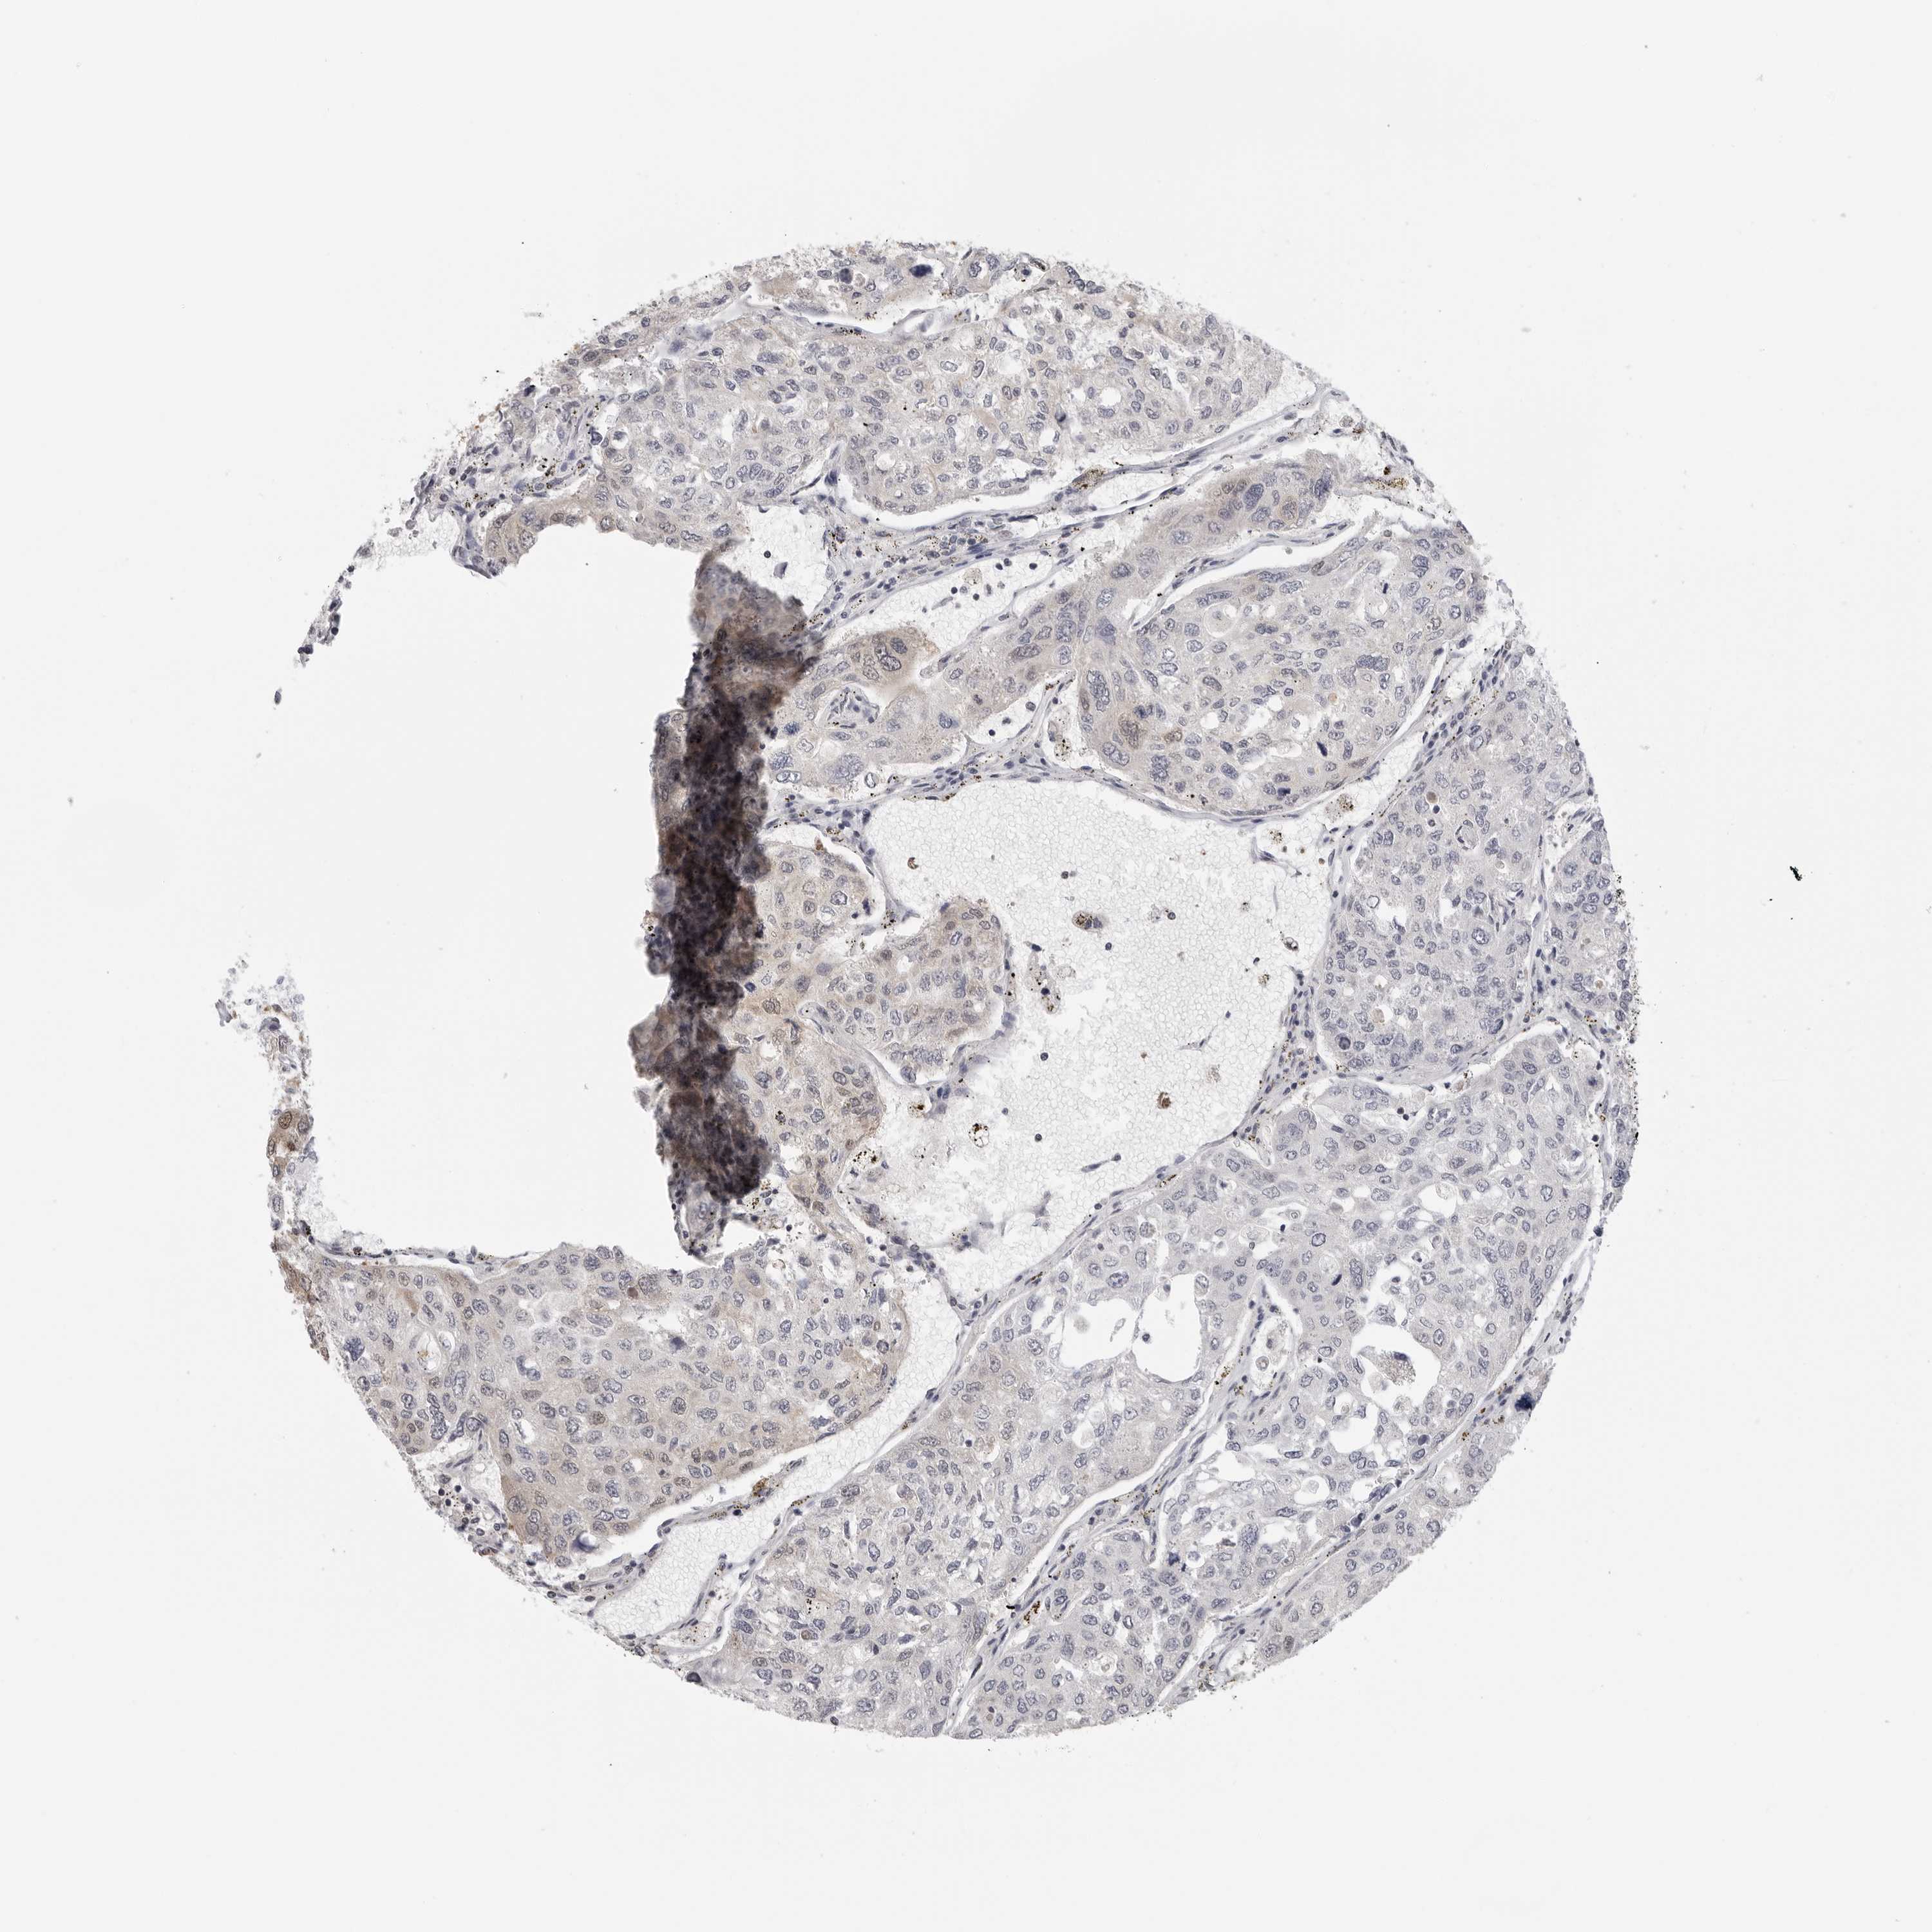

UROTHELIAL CANCER - Protein expressioni

A mouse-over function shows sample information and annotation data. Click on an image to view it in a full screen mode. Samples can be filtered based on level of antibody staining by selecting one or several of the following categories: high, medium, low and not detected. The assay and annotation is described here.

Note that samples used for immunohistochemistry by the Human Protein Atlas do not correspond to samples in the TCGA dataset.

Antibody stainingi

Antibody staining in the annotated cell types in the current human tissue is reported as not detected, low, medium, or high, based on conventional immunohistochemistry profiling in selected tissues. This score is based on the combination of the staining intensity and fraction of stained cells.

Each image is clickable and will lead to virtual microscopy that enables deeper exploration of all samples and also displays staining intensity scores, fraction scores and subcellular localization as well as patient and tissue information for each sample.

Antibody HPA026306

Antibody HPA026309

Antibody CAB016538

Staining

High

Medium

Low

Not detected

Intensity

Strong

Moderate

Weak

Negative

Quantity

>75%

75%-25%

<25%

None

Location

Nuclear

Cytoplasmic/membranous

Cytoplasmic/membranous,nuclear

Urothelial carcinoma, Low grade

Urothelial carcinoma, High grade